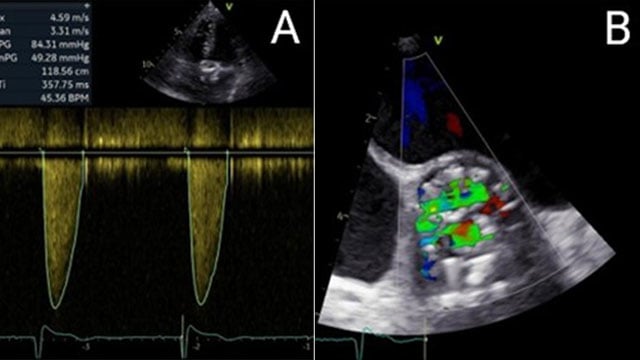

Severe MR in a high-risk patient with a suboptimal anatomy for M-TEER: what other options can we find?

Multimodality imaging reveals fibro-calcific leaflet disease, restricted motion, and a short posterior leaflet, making him a suboptimal candidate for M-TEER and prompting consideration of transcatheter mitral valve replacement. How would you treat?